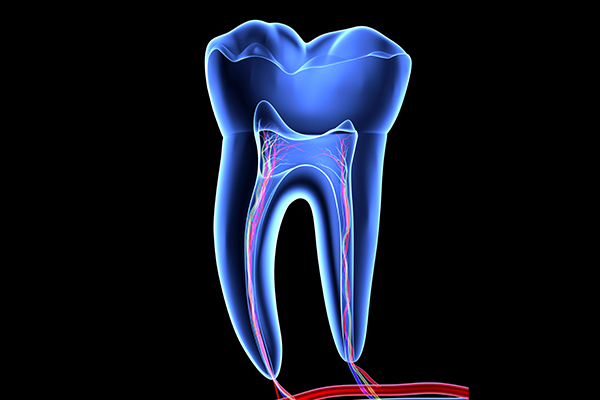

자연치아를 살리는

신경치료

신경치료는 치아의 신경(치수)이 충치의 세균에 의해 감염되거나 유해한 자극 등의 이유로 염증이 발생한 경우 손상된 신경조직 제거 및 신경과 혈관이 차지하고 있는 부위를 깨끗하게 제거하고 그 부위에 적합한 재료로 채워 넣는 치료를 말합니다.